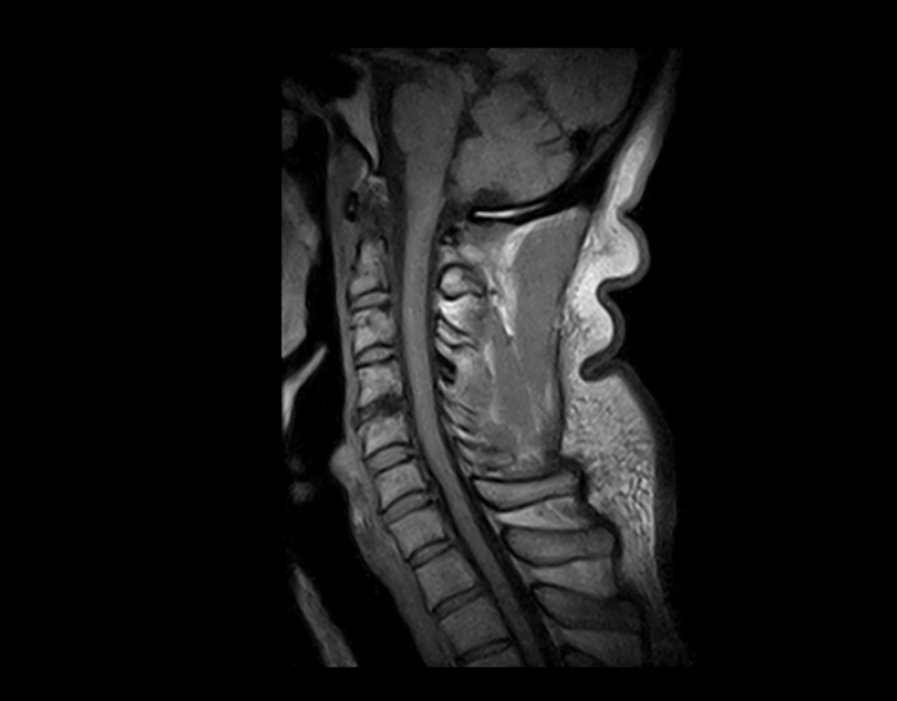

Esaote ha diseñado el sistema S-scan, que incluye la tecnología eXP, un escáner de resonancia magnética optimizado que cubre toda la anatomía musculo esquelética, desde el pie hasta los hombros, pasando por los segmentos más importantes de la columna, como la columna lumbar y cervical.

Imágenes Clínicas

El S-scan permite resonancias magnéticas cerebrales gracias a su amplia gama de aplicaciones a través de bobinas dedicadas.